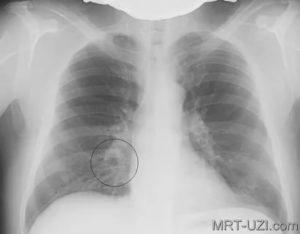

Первый признак пневмонии на рентгеновском снимке – появление очагов затемнения с неровными контурами в разных частях легкого, которые могут иметь разный размер, от 3-4-х до 12 мм.

Тени различают по внешнему виду (круглые, овальные кольцевидные) и интенсивности окраски – чем темнее пятно, тем сильнее выражен патологический процесс.

Расшифровать данные рентгеновского снимка способен только опытный рентгенолог. Также необходимо знать, что основным рентгенологическим признаком воспаления легких является участок или участки затемнения легочного поля. Однако, здоровые легкие на снимке имеют темный цвет, в то время как затемнения являются белыми участками.

Размеры очагов поражения в среднем достигают полутора сантиметров, при отсутствии лечения их количество увеличивается. На фото ниже изображен пример правосторонней очаговой пневмонии.